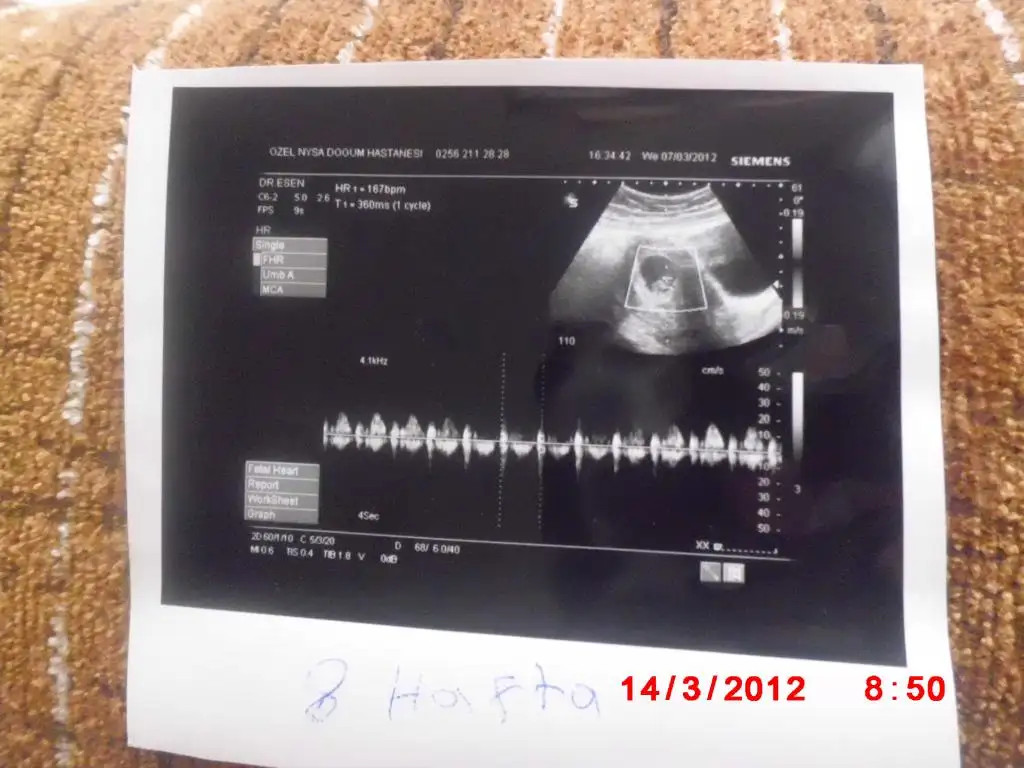

bugün sizlere bebişimin 8 haftalık ultrason resmini paylaşmak istedim

Eki Görüntüle 367104

Eki Görüntüle 367105

Eki Görüntüle 367103